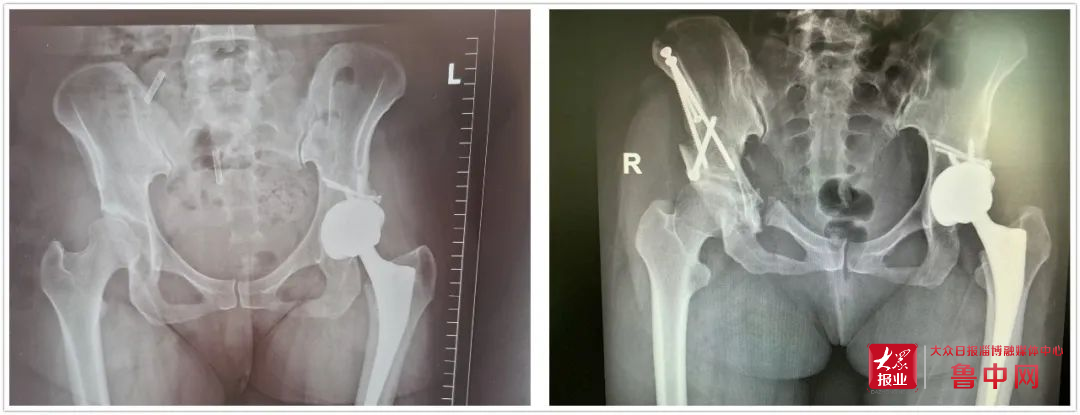

大眾日報淄博融媒體中心·魯中網(wǎng)2月23日訊(記者 荊睿 蓋思羽 通訊員 張騰)近日,北大醫(yī)療淄博醫(yī)院骨外科在山東第一醫(yī)科大學第一附屬醫(yī)院骨關(guān)節(jié)外科教授李樹鋒的指導下,成功為一名患者實施醫(yī)院首例髖臼周圍截骨術(shù)。該項技術(shù)的成功開展,填補了淄博市在治療成人先天性髖關(guān)節(jié)發(fā)育不良的手術(shù)空白。

骨外科主任方俊英接診胡女士后,對其進行詳細的問診和查體,并結(jié)合拍片檢查發(fā)現(xiàn)了右髖已出現(xiàn)輕度的關(guān)節(jié)炎。出于有過同樣手術(shù)經(jīng)歷的胡女士,深知全髖關(guān)節(jié)置換術(shù)的“后遺癥”。于是胡女士向方主任求助是否有更佳治療方案。方主任得知其顧慮后,立即組織骨外科專家對胡女士的病情進行討論,結(jié)合胡女士的影像資料及癥狀,考慮行髖臼周圍截骨術(shù)是最佳治療方案,既可以緩解癥狀,又可以延緩骨關(guān)節(jié)炎的發(fā)展,延期甚至無需接受全髖關(guān)節(jié)置換術(shù)。但因其髖臼周圍解剖復雜、手術(shù)難度大,目前能做此手術(shù)的專家甚少,北大醫(yī)療淄博醫(yī)院合作的山東第一醫(yī)科大學第一附屬醫(yī)院,骨關(guān)節(jié)外科李樹鋒主任正是其中一位。于是通過遠程會診系統(tǒng)在線邀請李樹鋒主任會診,結(jié)合患者病情,為其制定了詳細的手術(shù)方案。

經(jīng)過完善的術(shù)前準備,手術(shù)如期進行。術(shù)中經(jīng)過多次精確測量和截骨,在透視下逐一完成髂骨、恥骨支的截骨。在最難實施的坐骨支截骨階段,李樹鋒主任、方俊英主任以及骨外科專家團隊克服了坐骨周圍肌肉和深部組織的影響,完成了坐骨—髂骨截骨銜接,并一舉旋轉(zhuǎn)固定成功。手術(shù)經(jīng)歷三個多小時順利完成。在醫(yī)護人員的精心治療下,術(shù)后1周恢復良好,康復出院。